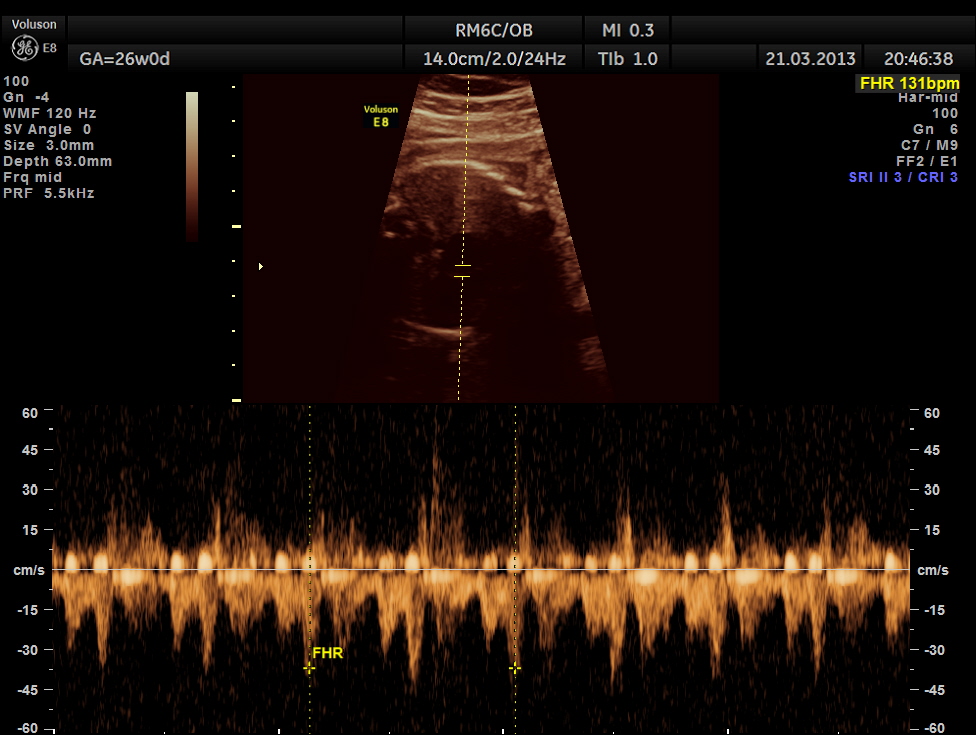

the following picture shows a probable transmitted rhythm with severe bradycardia

the following picture shows a normal conduction and rate